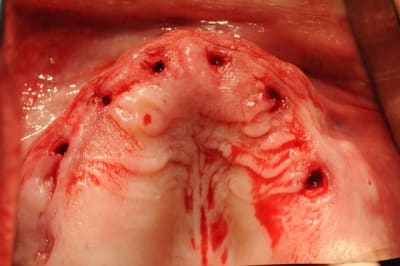

C'est une question que je me pose, car je viens de faire un cas comme ça mercredi matin.

Étant donné que j'avais une autoroute en matière de crête osseuse, je me suis dis " et puis zut, restons dans le couloir prothétique et plantons en aveugle".

Une bonne connaissance du scan était nécessaire, et des petits contrôles radios pendant la pose bien évidemment pour connaître la longueur de perçage et savoir quand mon implant allait être juxta-crestal.

- J'ai trouvé ça super de ne pas avoir à faire de sutures

- l'un des implants est volontairement incliné car il vient longer le plancher sinusien. Je n'avais pas envie de faire de Summers et le patient ne voulait pas de soulevé de sinus.

Je ne pense pas qu'on puisse le faire chez tous le monde, mais là, j'avais de la crête, de la gencive attachée et de l'os à profusion...

je n'ai pas utilisé de tissu punch donc pas de carotte ...

d'où ma question, les chances d'ostéointégrations sont elles réduites.

Je n'arrive pas à trouver une étude sur le devenir des éventuels cellules transportées le long de l'implant.